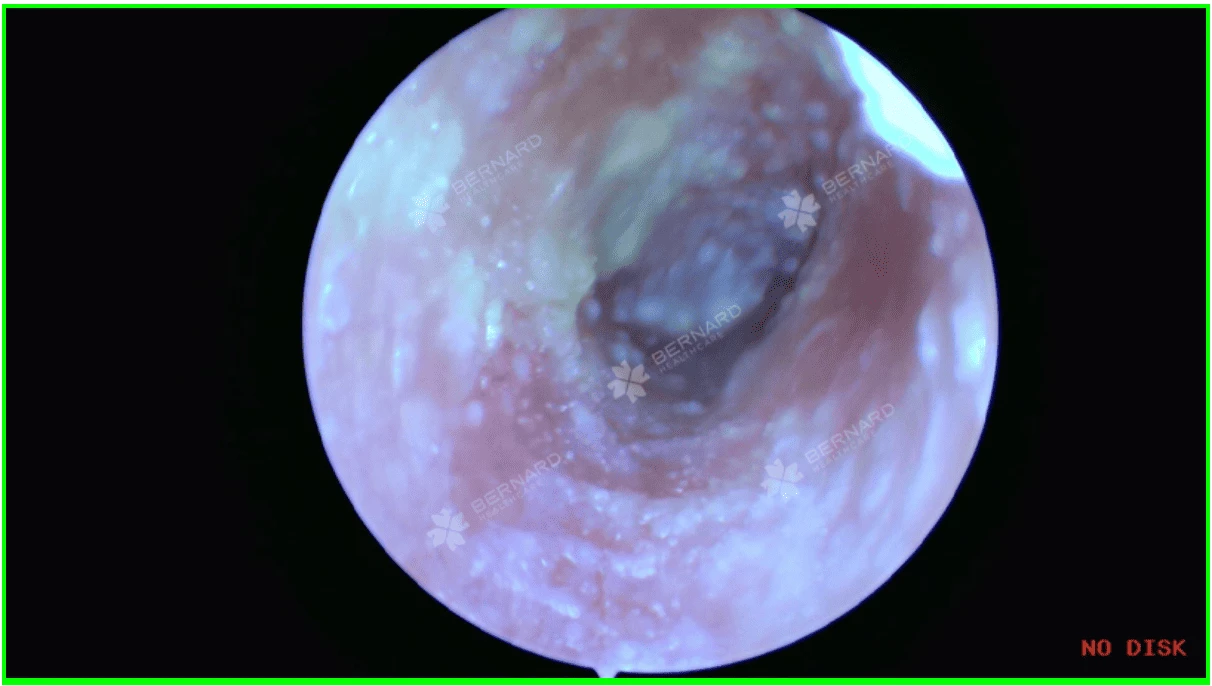

Nam khách hàng được Bác sĩ CKI. Trần Xuân Nguyên - Chuyên khoa Tai-Mũi-Họng, Bernard Healthcare trực tiếp thăm khám và chỉ định nội soi ống tai. Kết quả cho thấy, ống tai ngoài ở cả hai bên có tình trạng sung huyết, rải rác các mảng ráy tai kèm nấm. Màng nhĩ hai bên vẫn nguyên vẹn, tam giác sáng rõ, hòm nhĩ đóng ít mủ kèm nấm nhưng không đọng dịch.

- Ống tai ngoài bị trầy xước nhẹ và có các sợi nấm bám vào da bên trong.

- Ráy tai khô, không chảy dịch nhưng có ít mủ đọng, đóng mảng vảy do nấm đã làm hẹp ống tai, gây ra các triệu chứng như ngứa, đau và giảm thính lực.

Sự thay đổi bên trong ống tai của bệnh nhân qua các lần thăm khám tiếp theo:

Nhờ sự đồng hành xuyên suốt của bác sĩ Nguyên qua tổng cộng 5 liệu trình điều trị và tái khám, bệnh nhân đã hoàn toàn chấm dứt các triệu chứng ngứa ngáy khó chịu, tình trạng nấm tai được kiểm soát tốt và không tái phát, chức năng nghe được cải thiện rõ rệt.